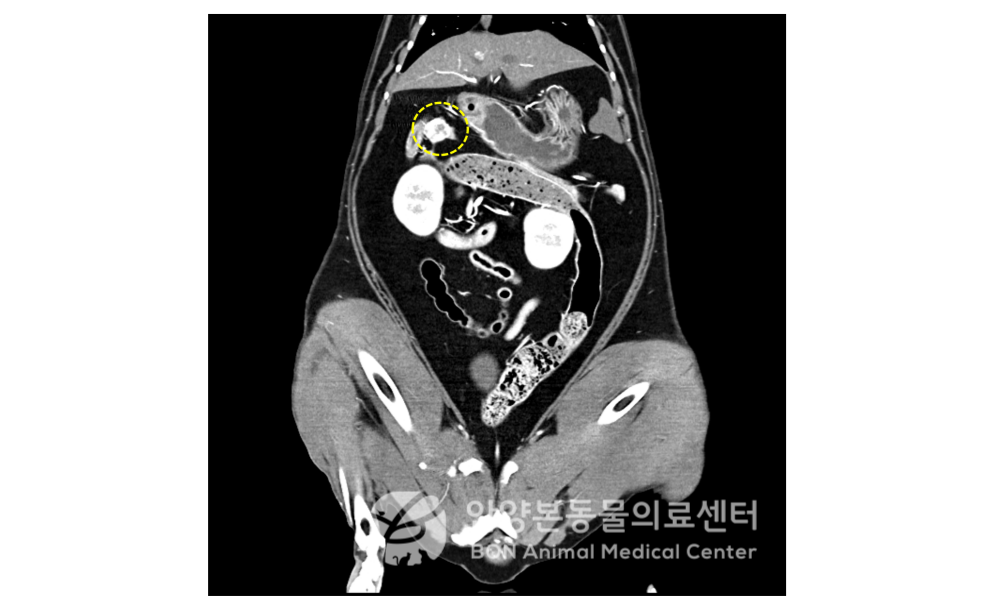

CT 검사 상 췌장 우측 다리에서 몸통 수준의 약 1.2 * 1.5 * 1.6 cm 크기의 종괴가 확인되었습니다.

[CT 검사 결과]